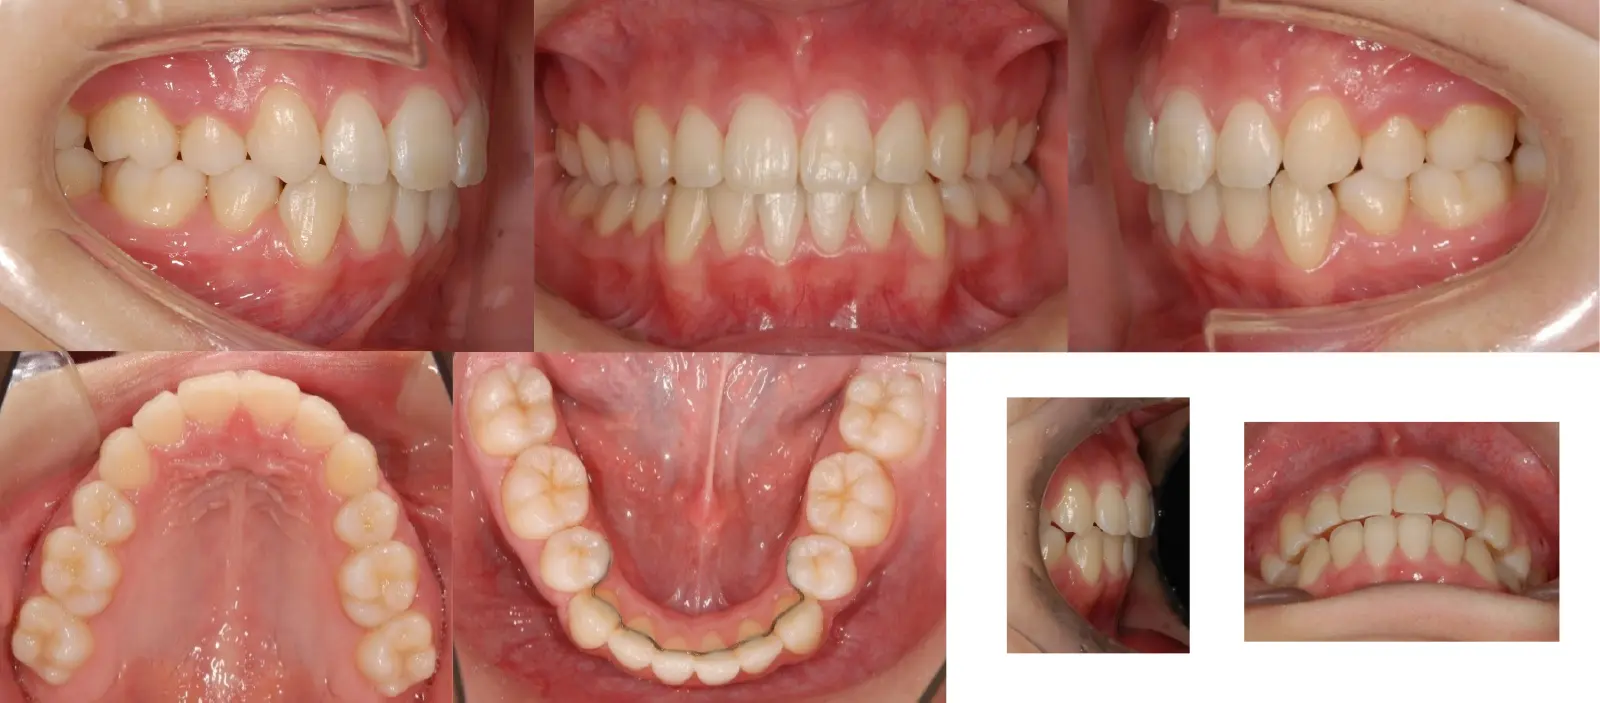

アングル1級叢生と過蓋咬合を伴う上顎前突症

- 主訴

口元の突出感と乱食歯

- 年齢

10代

- 治療期間

1年5ヶ月

- 治療回数

16回

- 治療に用いた主な装置

カスタムメイド型マルチブラケットタイプのデジタル矯正装置(インシグニア)

- 治療費

630,000円(税別)、調整料5,000円(税別)

- 抜歯部位

上下顎第一小臼歯 計4本